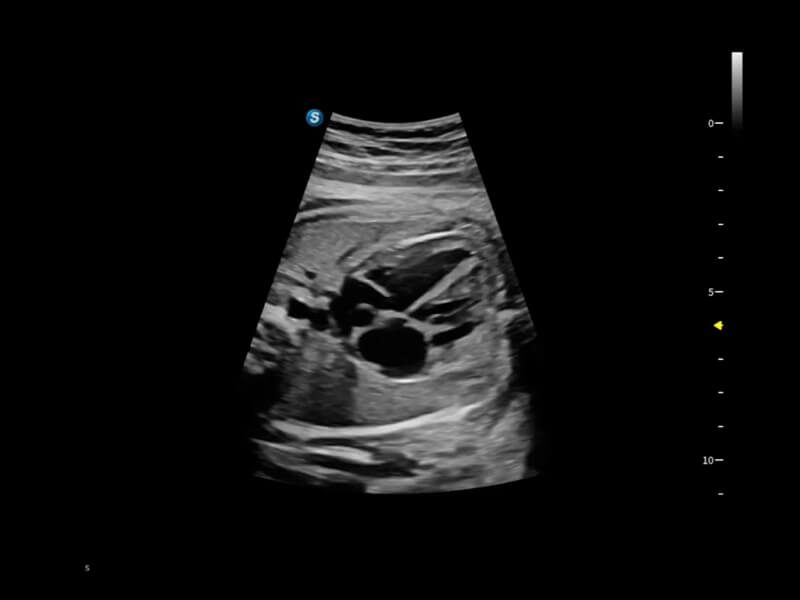

豐富的血流動(dòng)力學(xué)檢測(cè)技術(shù),可在不同醫(yī)療場(chǎng)景中高效捕捉血流信號(hào),助力臨床診療。

在傳統(tǒng)血流的基礎(chǔ)上優(yōu)化掃查和算法策略,能夠更好的抑制組織信息,提煉紅細(xì)胞運(yùn)動(dòng)信息,得到更高幀頻,高靈敏度和分辨率的血流信號(hào),還原更真實(shí)的血流動(dòng)力學(xué)。